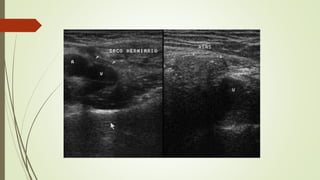

ECOGRAFÍA

 Transductor lineal 7 – 10 MHz

 Escala de grises:

 Asas intestinales con peristaltismo dentro de la hernia inguinal.

 Supino / bipedestación / Valsalva

Valsalva:

 Hernia inguinal directa: plexo pampiniforme distendido se

ve desplazado por el saco herniario.

 Hernia inguinal indirecta: ingurgitación alterada del plexo

pampiniforme.

 Doppler color:

 Demuestra la arteria epigástrica inferior y la relación con el saco

herniario.

 Hernia estrangulada.

HERNIA DIRECTA

 Pasa anteromedial a vasos epigástricos inferiores

 Masa lateral a músculo recto

 «Signo lateral cresciente»

 CI desplazado y comprimido lateralmente, incluyendo grasa y demás

contenidos

HERNIA INDIRECTA

 Pasa superolateral a vaso epigástrico inferior  lateral y medial

siguiendo el CI

 Se muestra con el contenido habitual del CI, no se comprime ni

distorsiona